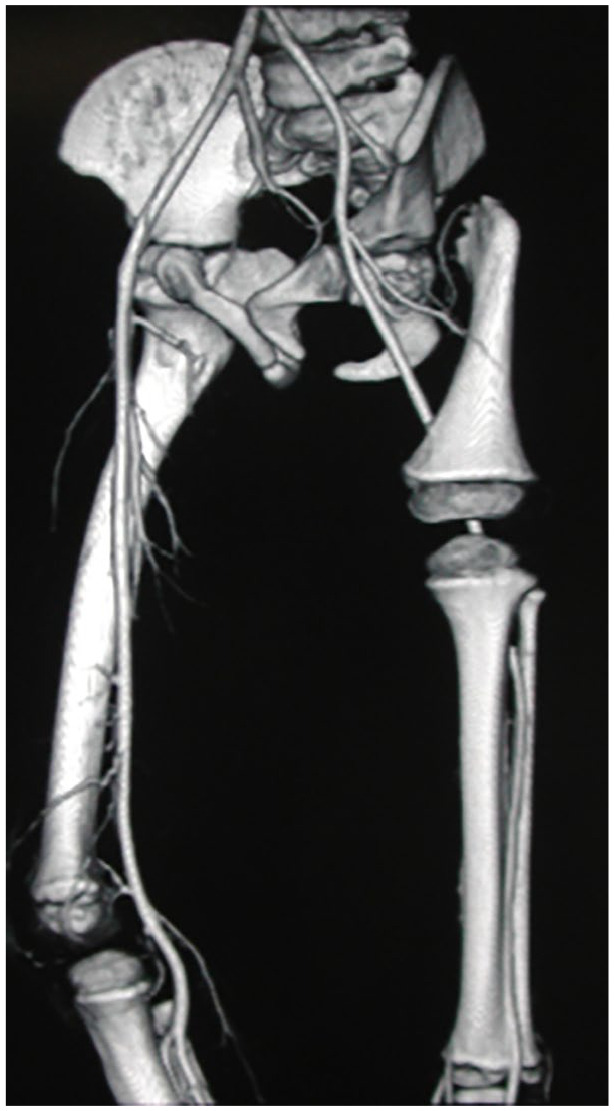

目的:描述股骨近端局灶性缺陷足部异常及其与严重程度的关系。方法:对1996 ~ 2020年87例患者89条肢体进行临床及影像学评价。记录腓骨长度、踝关节形状、跗骨联合以及足射线的数量。将股骨近端局灶性缺损肢体按Pappas分类,分为重度组(II、V级)、中度重度组(III、IV级)和轻度组(VII、VIII、IX级)。结果:89%的患者腓骨短,11%的患者腓骨缺失。腓骨缺失主要发生在严重的III级,仅发生在轻度级别的4%(有统计学意义,p = 0.004)。踝关节外翻占82%。球形踝关节(18%的病例)在所有病例中都与跗骨联合有关。14.6%发生跗骨联合,除IV类外,所有类别均有。83%的病例有5个射线足,16%的病例有4个射线足,一个肢体有3个射线足。足部射线次数减少更常见于腓骨发育不全患者(30%)。结论:腓骨和踝关节异常是股骨近端局灶性缺陷的一部分,而跗骨联合和足部射线减少则不是。足部畸形的严重程度与股骨近端局灶性缺陷的严重程度无关,但与腓骨发育不全有关。

Results: The fibula was short in 89% and absent in 11% of cases. An absent fibula occurred mostly in severe class III and only in 4% of mild grades (statistically significant, p = 0.004). The valgus ankle joint prevailed in 82% of cases. Spherical ankle joints (18% of cases) were associated in all cases with a tarsal coalition. Tarsal coalitions occurred in 14.6% and were present in all classes except class IV. Five ray feet were found in 83% of cases, four ray feet were found in 16%, and three ray feet in one extremity. Reduction in the number of foot rays occurred more commonly in association with fibular aplasia (30%).

Conclusions: Abnormalities of the fibula and ankle joint represent a constant part of proximal femoral focal deficiency, whereas tarsal coalition and a reduction of foot rays do not. The severity of foot abnormalities does not correlate to the severity of proximal femoral focal deficiency but does with fibular aplasia.